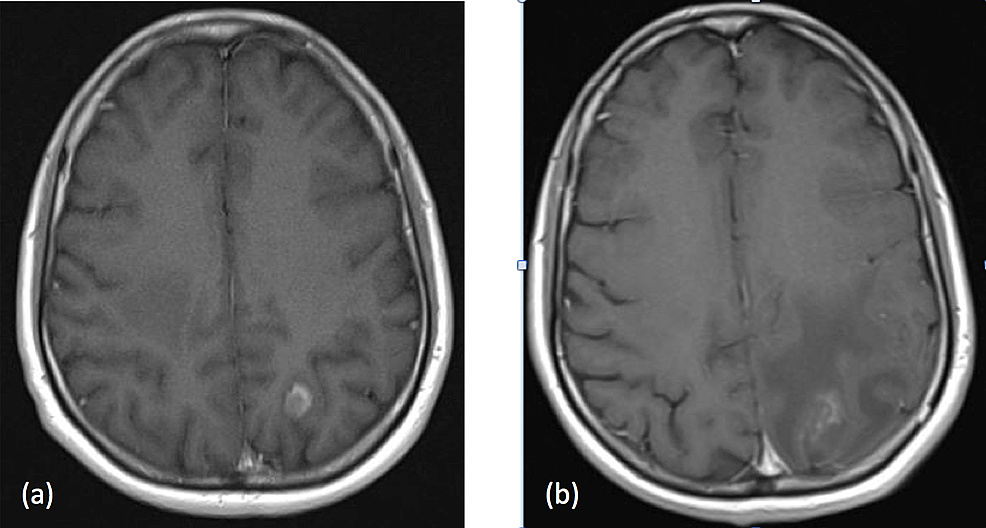

From www.researchgate.net

Pre and post radiosurgery Cerebral metastatic lesion (a)... Download Radiosurgery Brain Lesions There are different types of technology used in. Stereotactic radiosurgery is a method of delivering radiation to brain tumors. Find out whether you might be a good candidate for this alternative to. Stereotactic radiosurgery is a very precise form of therapeutic radiation that can be used to treat abnormalities in the brain and spine, including cancer, epilepsy, trigeminal neuralgia and.. Radiosurgery Brain Lesions.